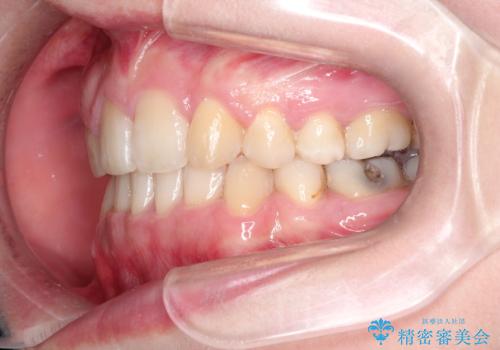

犬歯が変な位置にある 抜歯矯正により正しい位置へ

犬歯も通常の位置にまで移動することができ、口元もすっきりすることができました。